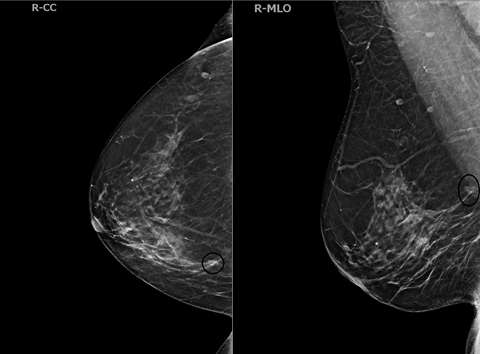

- Mammography/Digital Breast Tomosynthesis (DBT):

ILC cells preserve the architecture of ducts, limiting the detection of mammography. The sensitivity of mammography is 57-81%, with up to 30% of cases not at all visible, while the specificity is 34%1. The most common mammographic presentations are a mass with spiculated or indistinct margins (44%-65%) and architectural distortions (10-34%)1. Some less common findings are asymmetries, focal asymmetries, and shrinking breast appearance over time. DBT produces thinner slices and thus reduces the tissue masking effect of mammography. These two modalities are described together in the literature for ILC detection rates.

Case 2: